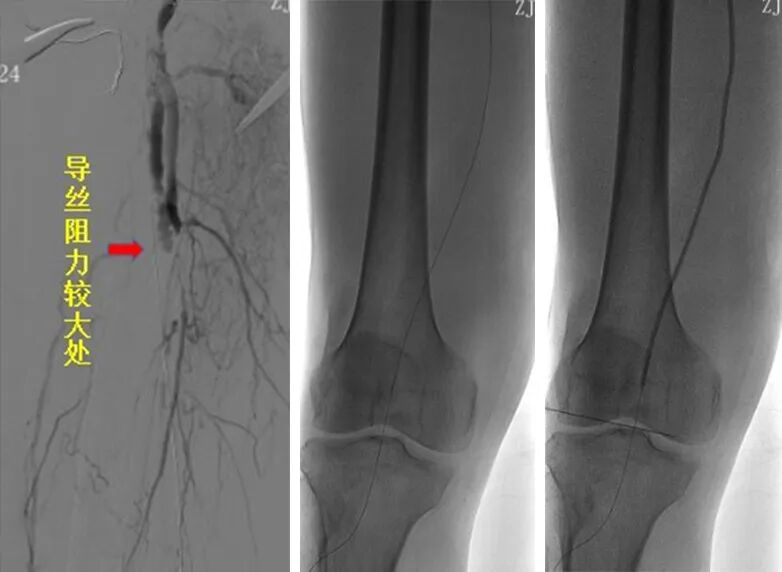

2、交换6F翻山鞘后,单弯导管配合导丝拟开通右股浅动脉病变,术中开通右股浅动脉近端时阻力较大,单弯导管配合泥鳅导丝下行距分叉5cm左右处下行困难,遂交换0.035系统支撑导管成袢下行通过。

(1)该病变的形成原因:一种考虑医源性夹层动脉瘤可能(导丝导管过该病变段时阻力大且导丝多次成袢过,下行时较为不畅);另一种考虑是否为血管本身病变引起。

医疗组再次调阅术前CTA影像横断面:右股浅近端此区域存在血管扩张样改变(见下图)